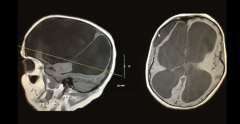

脑积水 ,是一种大脑和脊髓周围有额外的脑脊液的情况。脑脊液...

脑积水是一种过多的脑脊液留在脑腔中,导致大脑和颅骨肿胀的...

在产前发育过程中,大脑从管状结构开始。随着它的生长,内管...